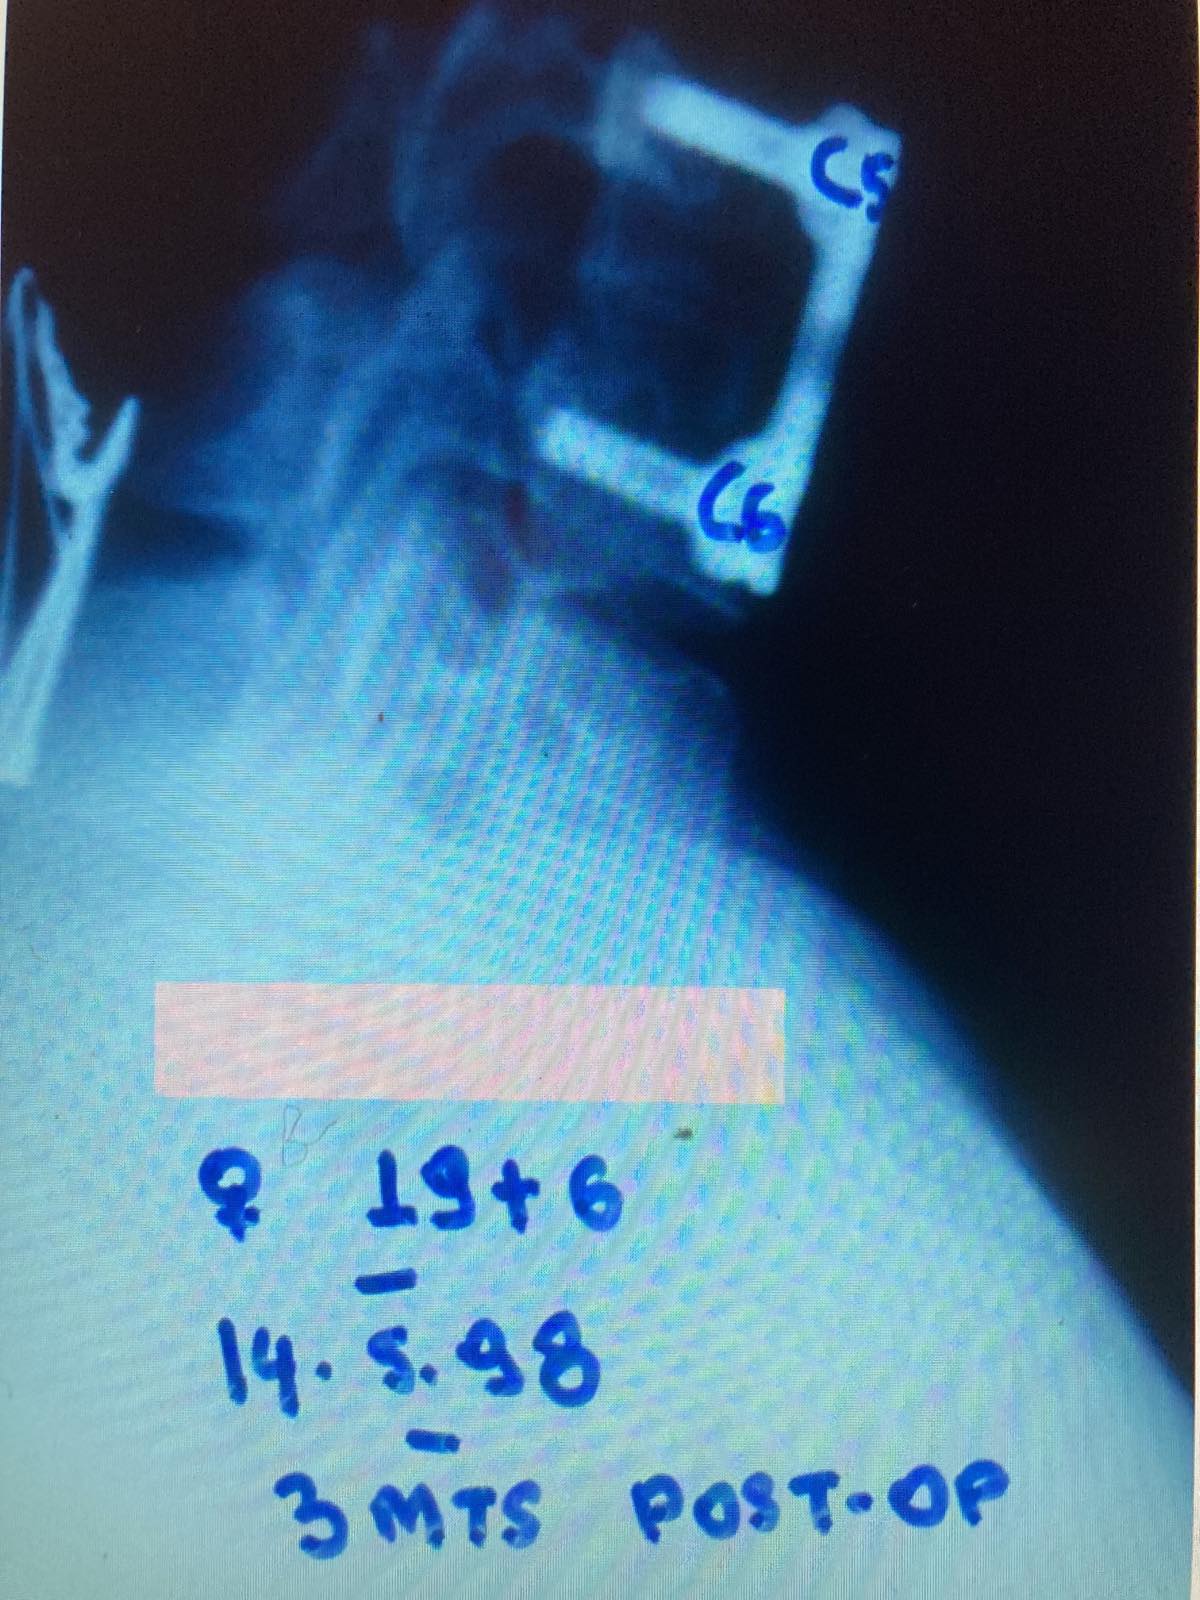

- α

- β

Εικόνα 10 (α, β)

Προσθιοπίσθια (α) και πλάγια (β) ακτινογραφία, τρείς μήνες μετεγχειρητικά. Παρατηρείται ότι υφίσταται σταθερότητα στην ΑΜΣΣ και ακεραιότητα των χρησιμοποιηθέντων υλικών σπονδυλοδεσίας.